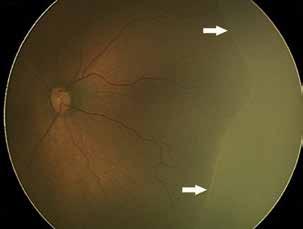

Type 3 MNV refers to the growth of vessels from the retinal circulation toward the outer retina. It is believed that vascular proliferation begins in the deep retinal capillary plexus, with the growth vector extending toward the outer retina. On FA and ICGA, Type 3 MNV appears as a hyperfluorescent intraretinal vascular complex with leakage in the late phases of the examination. Late-phase leakage ion ICGA is a unique feature of MNV lesions. Since these lesions originate from the retinal circulation, they never arise within the foveal avascular zone. Instead, they develop near its edge or at a variable distance from it, typically from the terminal portions of third-order arterioles and venules.5 (Figure 3)

Figure 3. Two examples of Type 3 macular neovascularization. In the first case, Indocyanine green angiography (B) and fluorescein angiography revealing the Type 3 macular neovascularization (arrowhead). Optical coherence tomography (C) showing the detachment of retinal pigment epithelium with the hyperreflective material related to the neovascularization. In the second case, optical coherence tomography (E) showing the intraretinal hyperreflective material related to the neovascularization with intraretinal fluid. Fundus autofluorescence (F) showing abnormalities of retinal pigment epithelium. Optical coherence tomography angiography (G) showing the neovascular lesion.